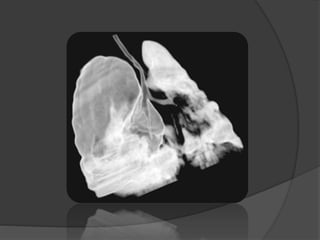

Imagerie: Radiographie du thorax

« KB

périphérique

infecté »